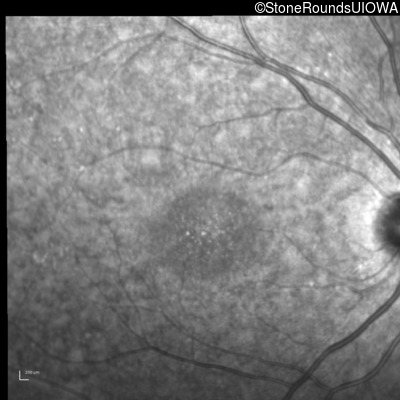

| AR Stargardt Disease | ABCA4 | IVS21-2 A>G | Pro1380Leu CCG>CTG | AR |